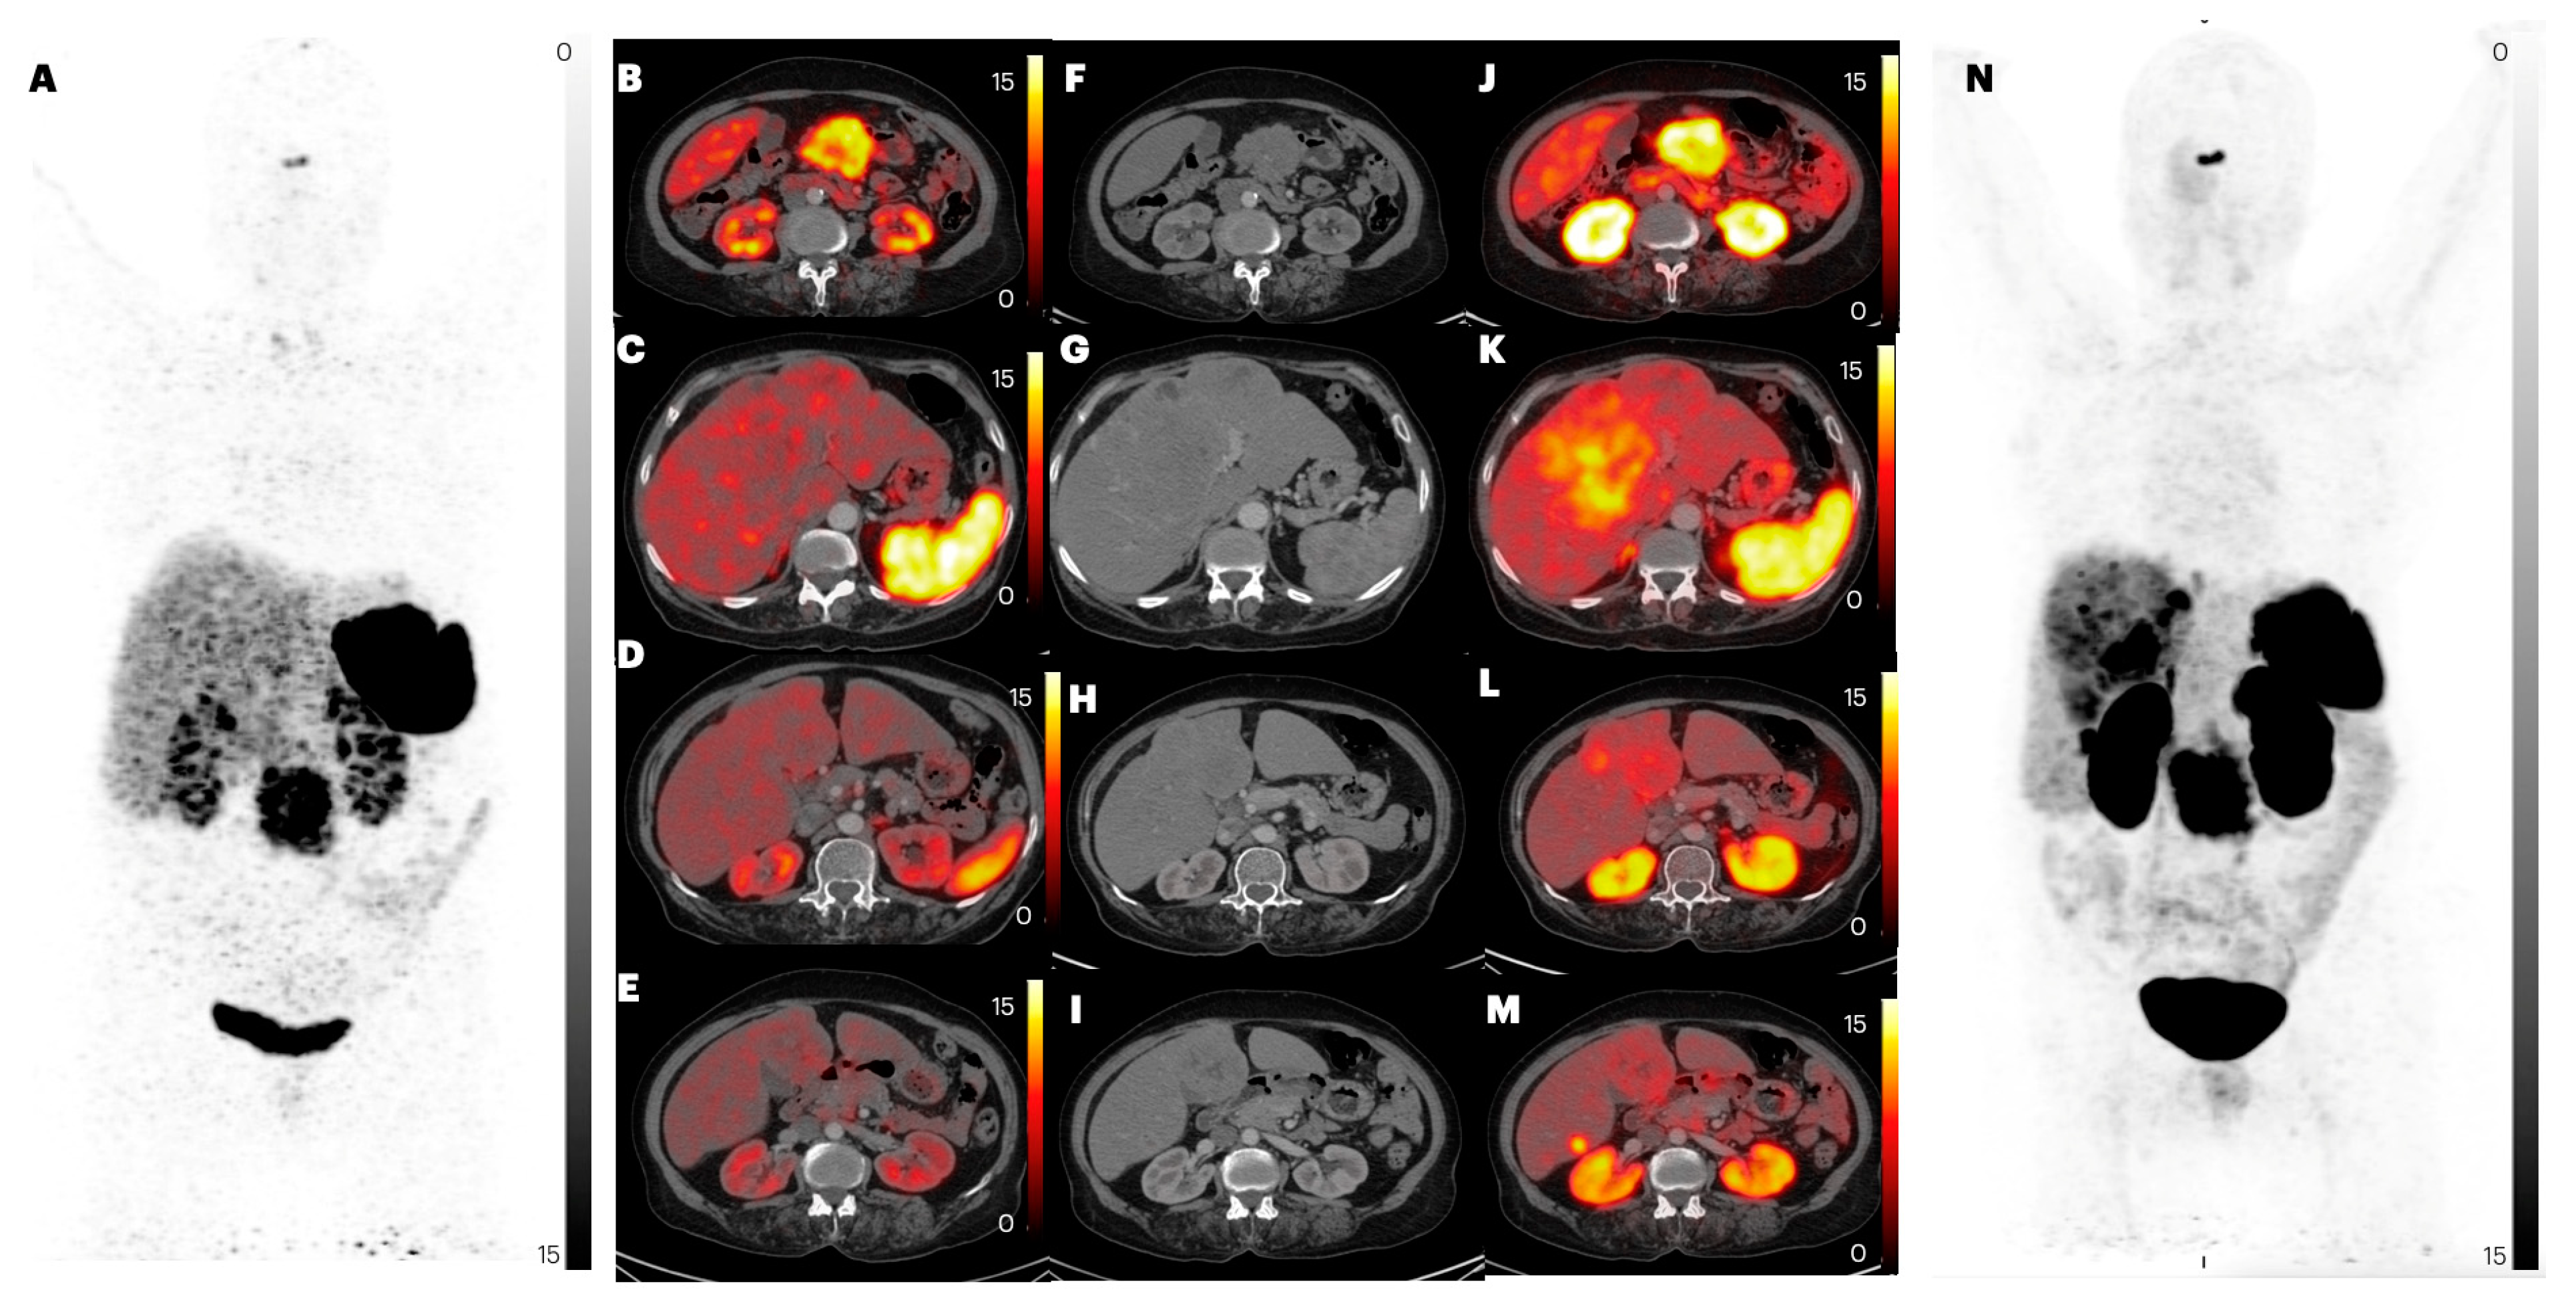

2.2.4. Liver Metastases

2.2. Comparison of Lesion Detection and Uptake between [68Ga]Ga-DOTANOC and [68Ga]Ga-DATA5m-LM4